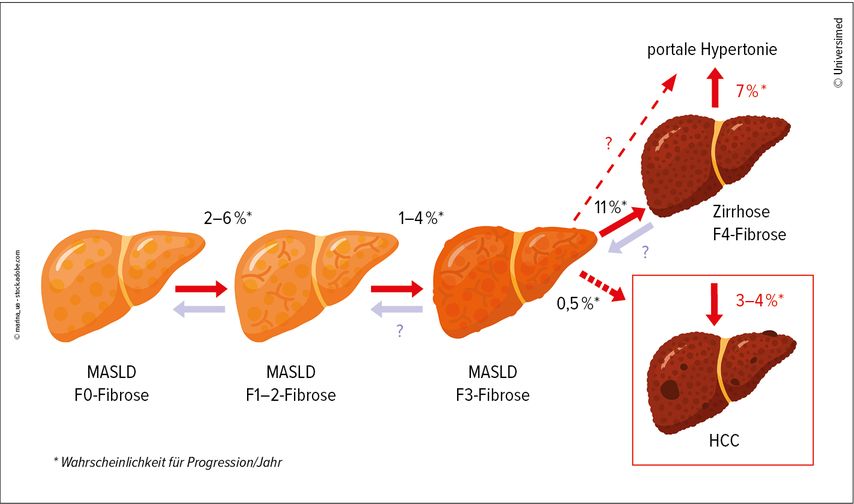

Etwa 25% der Allgemeinbevölkerung haben eine Steatose oder MASLD, bei Patient:innen mit Typ-2-Diabetes sind es 65% und bei Menschen mit Adipositas 80%.10 In der Schweiz sind laut Bundesamt für Gesundheit (BAG) mehr als 50% der Männer und 33% der Frauen übergewichtig oder adipös und entsprechend betroffen.11 Allerdings entwickeln nicht alle ein HCC, ein Risiko tragen vor allem Menschen mit einer hochgradigen Fibrose (Abb.1).12 Diese gilt es zu identifizieren. Dazu ist ein zweistufiges, nichtinvasives Screening geeignet. In der ersten Stufe wird anhand des Alters, der Transaminasenwerte und der Thrombozytenzahl der FIB-4-Score berechnet. Bei einem Score <1,3 sollte in der zweiten Stufe eine weitere Abklärung erfolgen, etwa durch eine Leberelastografie.13

Abb. 1: Progression chronischer Hepatopathien (z.B. MASLD) bis zum Endstadium mit Zirrhose und hepatozellulärem Karzinom (HCC)